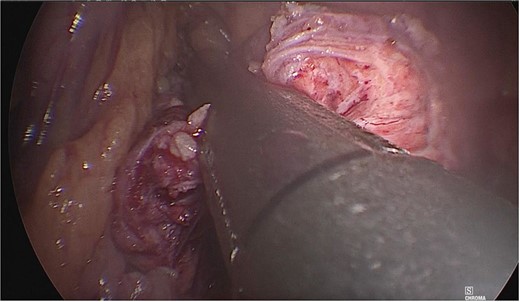

Once the above procedure was completed, it was dissected along the neck of the pancreas to identify the superior mesenteric vein and splenic vein. An incision was made along the superior border of the pancreas, to the left of the gastroduodenal artery and inferior to the hepatic artery. A plane was created between the portal vein and neck of the pancreas by blunt dissection from the inferior to the superior direction with a blunt-tipped laparoscopic dissector (Fig. 2).

A plane was created between the portal vein and the neck of the pancreas by blunt dissection.